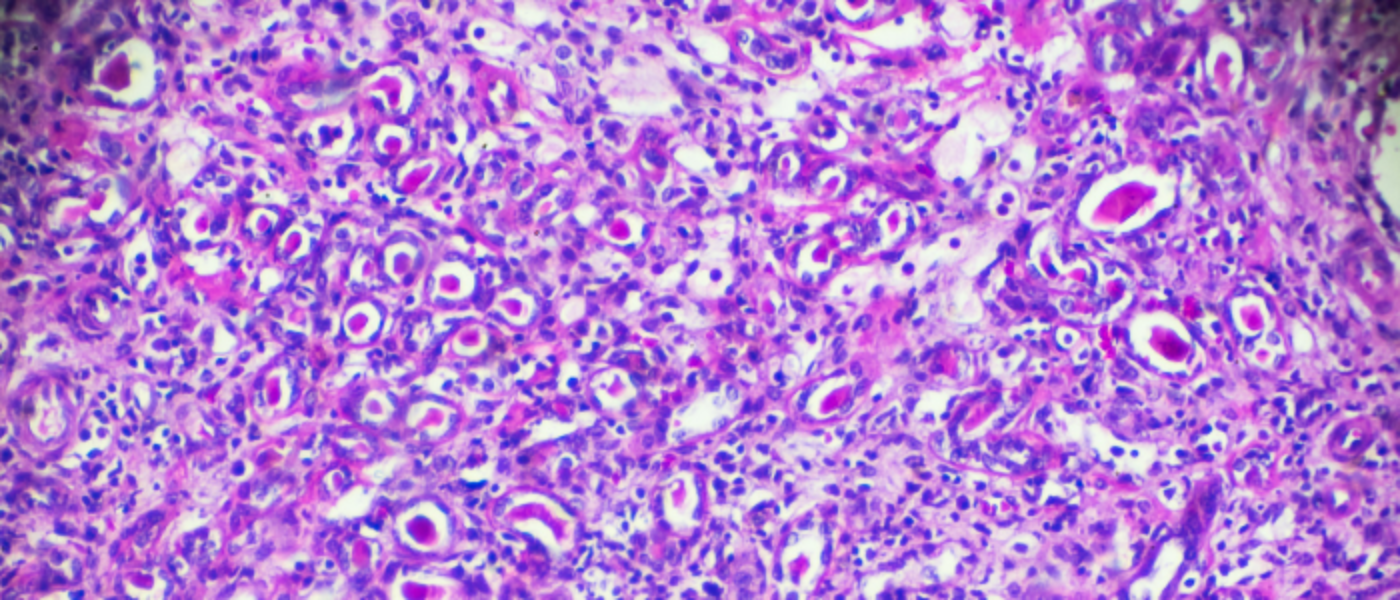

Glomerulonephritis in Runwal Nagar is a serious kidney condition where the tiny filters of the kidneys, called glomeruli, become inflamed. At Hope Kidney Care, accurate diagnosis and timely treatment help prevent long-term damage.

The nephrologists at Hope Kidney Care use blood tests, urine analysis, and kidney biopsy to confirm the diagnosis. Treatment depends on the cause but may involve medications to control inflammation, blood pressure, or immune response. In severe cases, dialysis or transplant evaluation may be needed.